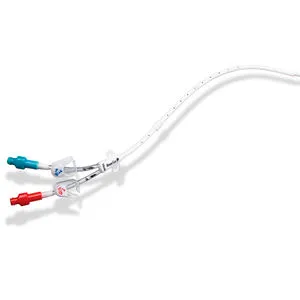

Intoxicação por citrato na contínua: quando suspeitar e como tratar

Intoxicação por citrato na contínua: quando suspeitar e como tratar